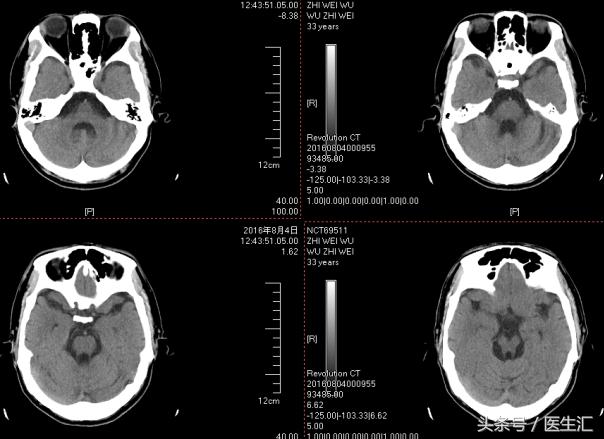

图像资料

核磁:小脑萎缩、脑干萎缩